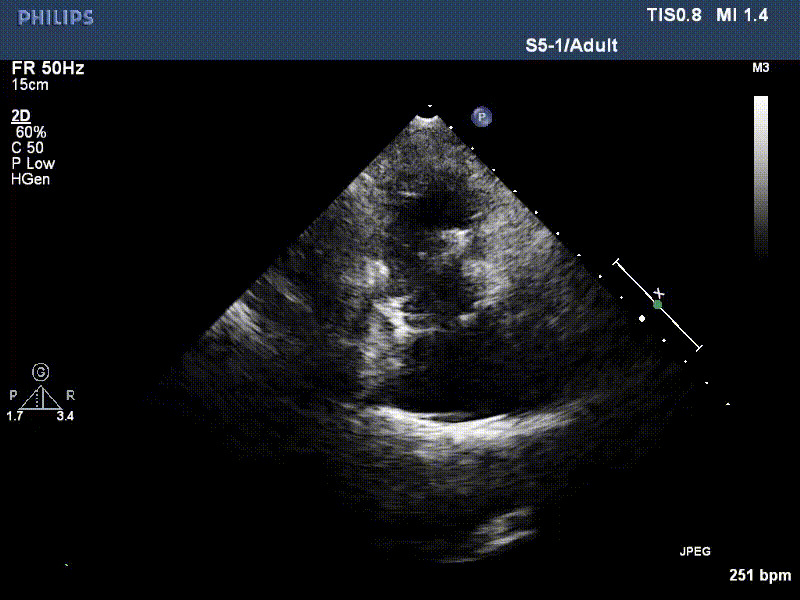

流并分別伴有房顫和房撲,高外科手術風險。術前超聲提示,兩例患者下腔靜脈寬度分別為13mm和29mm,右房內徑(上下徑和左右徑)分別為52×41mm和53×43mm,彩色多普勒顯示極重度三尖瓣反流,VCW分別為14×15mm和10mm。

1年前,兩例患者因難治性雙下肢水腫輾轉多家醫院尋求救治,考慮到兩例患者高齡、基礎疾病多、STS評分高,不適合傳統外科開胸手術,葛均波院士及其團隊周達新教授、潘文志教授、張源博士、陳莎莎博士、陳丹丹博士聯合心外科王春生、魏來主任,麻醉科繆長虹、郭克芳主任以及心超室的潘翠珍教授、李偉教授共同討論決定,采用我國創新器械LuX-Valve Plus經血管三尖瓣置換系統為患者進行手術。相較于第一代產品LuX-Valve,LuX-Valve Plus經血管三尖瓣置換系統對輸送系統進行了全面升級,實現了經頸靜脈入路的方式,進一步減小了手術風險和對患者的創傷。目前隨訪1年心超結果顯示,三尖瓣極重度反流消失,人工三尖瓣瓣膜穩定牢固,瓣葉活動度良好,右心室及下腔靜脈明顯縮小,心輸出量增加。兩位老人手術后沒有出現過胸悶氣促的癥狀,下肢水腫緩解,活動耐力提升,生活質量也大為提高。

圖2 患者植入LuX-Valve Plus后,1年隨訪心超提示無三尖瓣反流